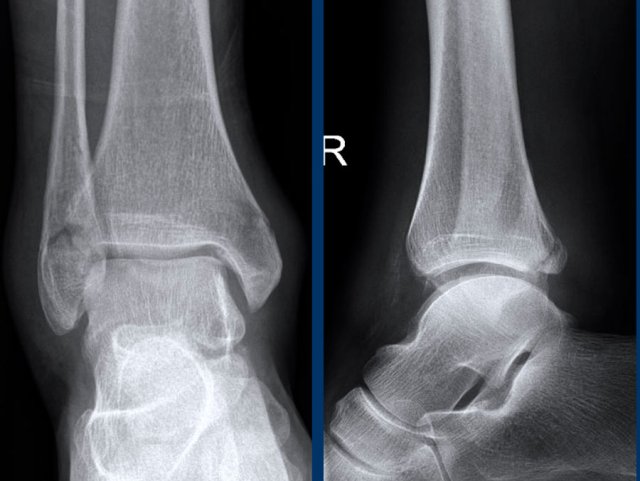

case 1 - ankle distortion

What are the findings and what does it mean?

Click on image for larger view.

Go to the discussion...